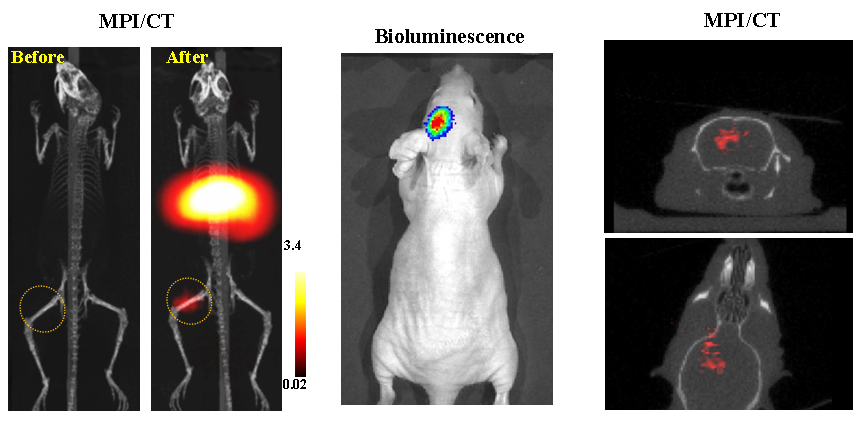

今年二月份,宋国胜教授与斯坦福大学饶江宏教授合作,通过系统的研究获得了影响磁性粒子成像信号的作用规律和关键原理,开发了新型磁性粒子探针---FeCo合金粒子,并首次应用于磁性粒子成像(MPI)。该造影剂在极低含量时(5 ng)仍具有很强的造影效果。这意味着,未来在进行人体成像时,可以使用更小剂量的造影剂,从而避免高剂量造影剂引起的肾肝损伤。基于MPI的直接成像原理,我们可以对造影剂进行正相和无背景干扰的活体成像,极大地提高信噪比。这项技术为肿瘤早期诊断、癌细胞示踪、脑中风、药物输送治疗、肺部灌注成像、胃肠出血、神经退行性疾病、磁热治疗等在活体中的可视化研究,提供了强有力的手段。相关研究成果以太阳集团城网站2017为第一单位发表在Nature 子刊《Nature Biomedical Engineering》。该期刊是“生物医学工程”的顶级期刊。宋国胜教授为该论文的共同通讯作者。